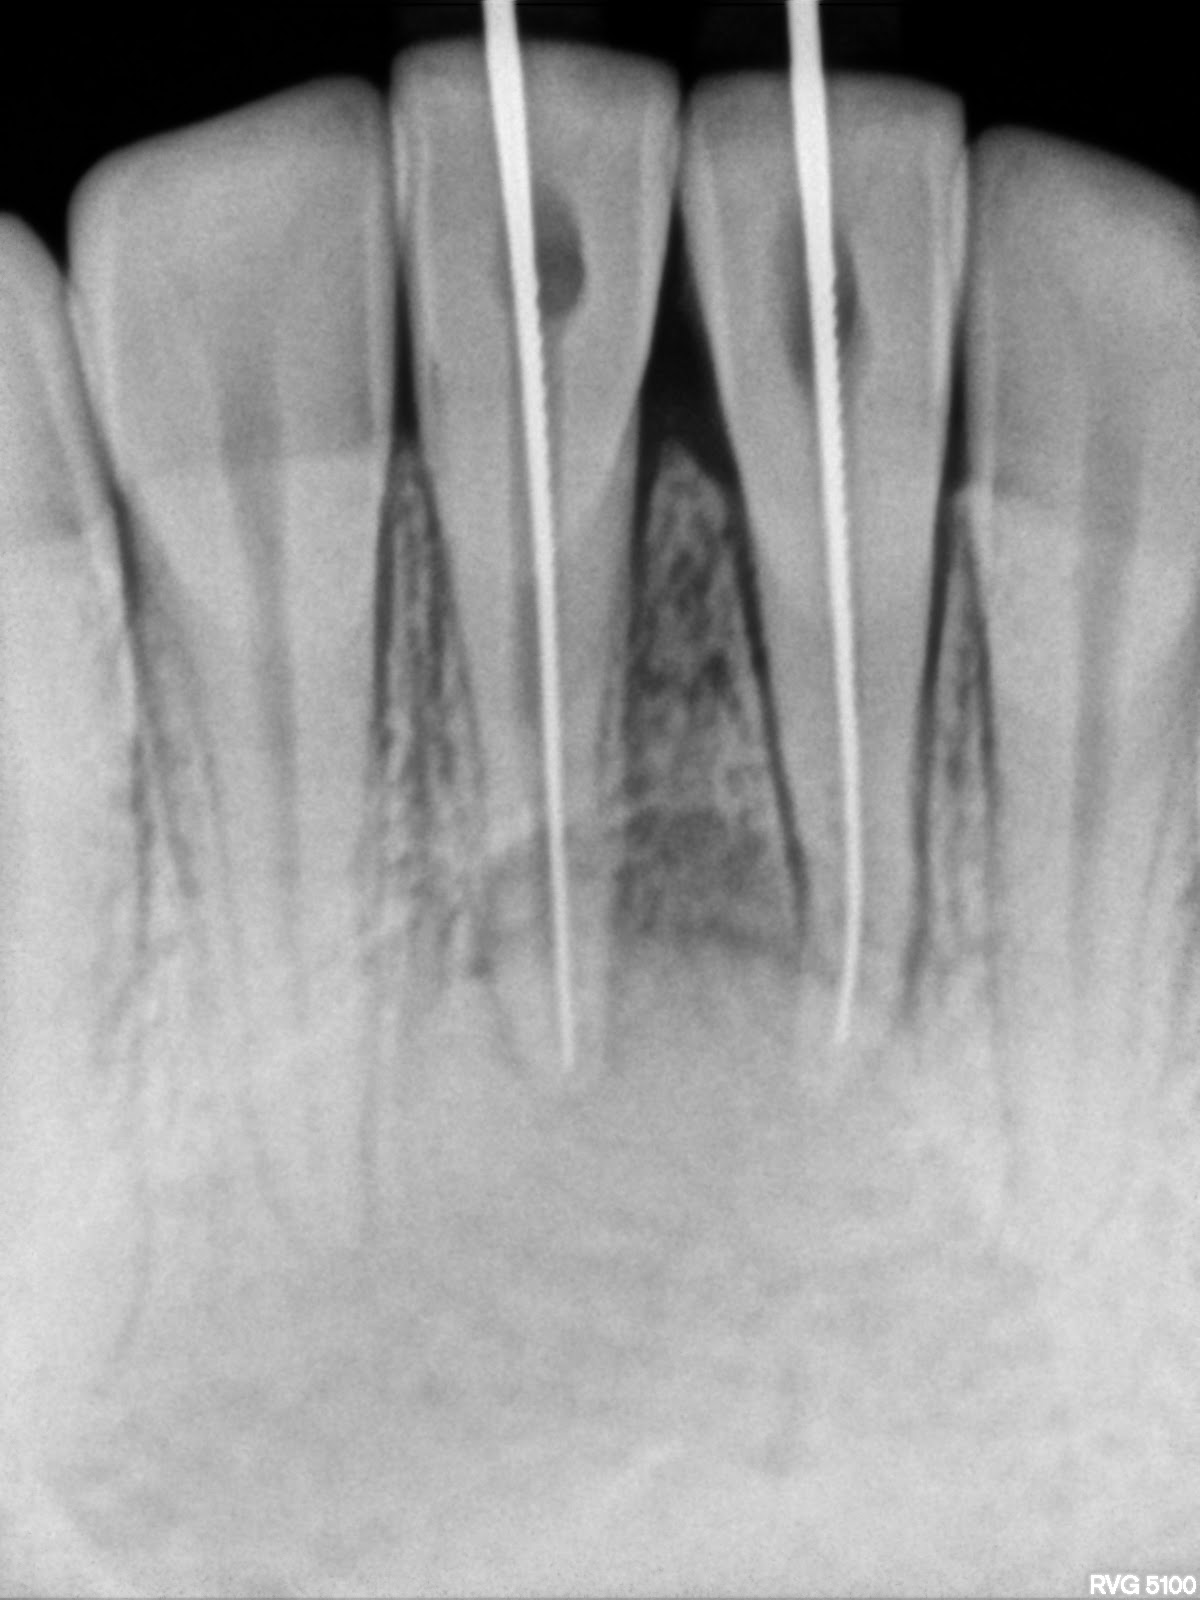

From www.researchgate.net

(a) Preoperative radiograph. (b) Working length radiograph. (c) Master What Is Master Cone In Rct Cone fit is the first step and a good starting point for a perfect 3d obturation of the root canal system. During this phase, we need: Learn how to perform a successful root canal treatment on a lower molar tooth in one visit using nickel titanium files, apex locator, gutta percha and thermoplastic. Learn how to fill a root canal. What Is Master Cone In Rct.